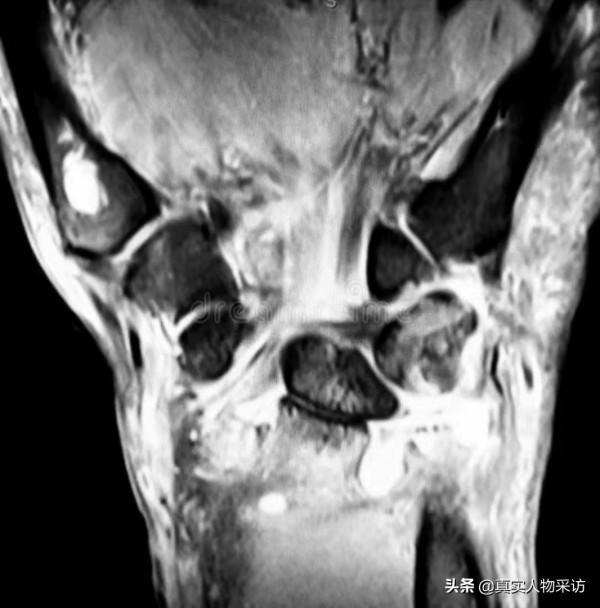

自從宗力走丟以後,我為了找兒子,早就把自己的腿跑壞了。不僅半月板磨損得厲害,還得了滑mo炎,積液多得腳都抬不起來,經常要往外抽積液。